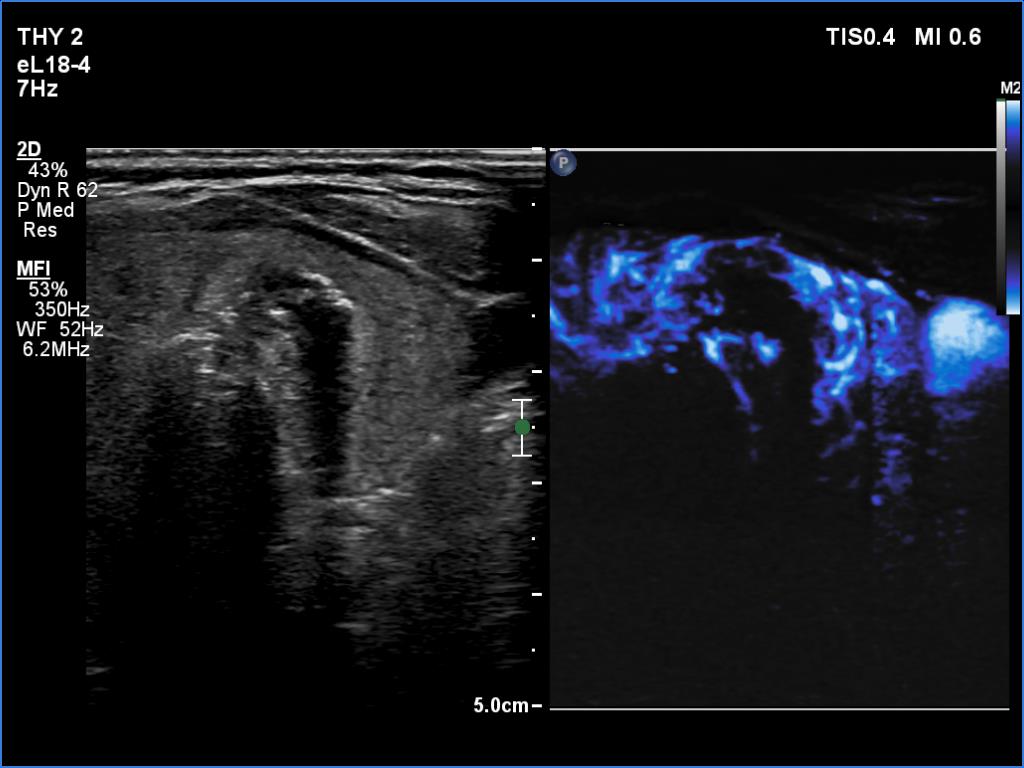

Ultrasonography. There was an irregular, large hypoechoic mass in the right lobe. The nodule has irregular, lobulated margins and was hard on elastography. A much smaller, similar nodule was in the lower-medial part of the left lobe.